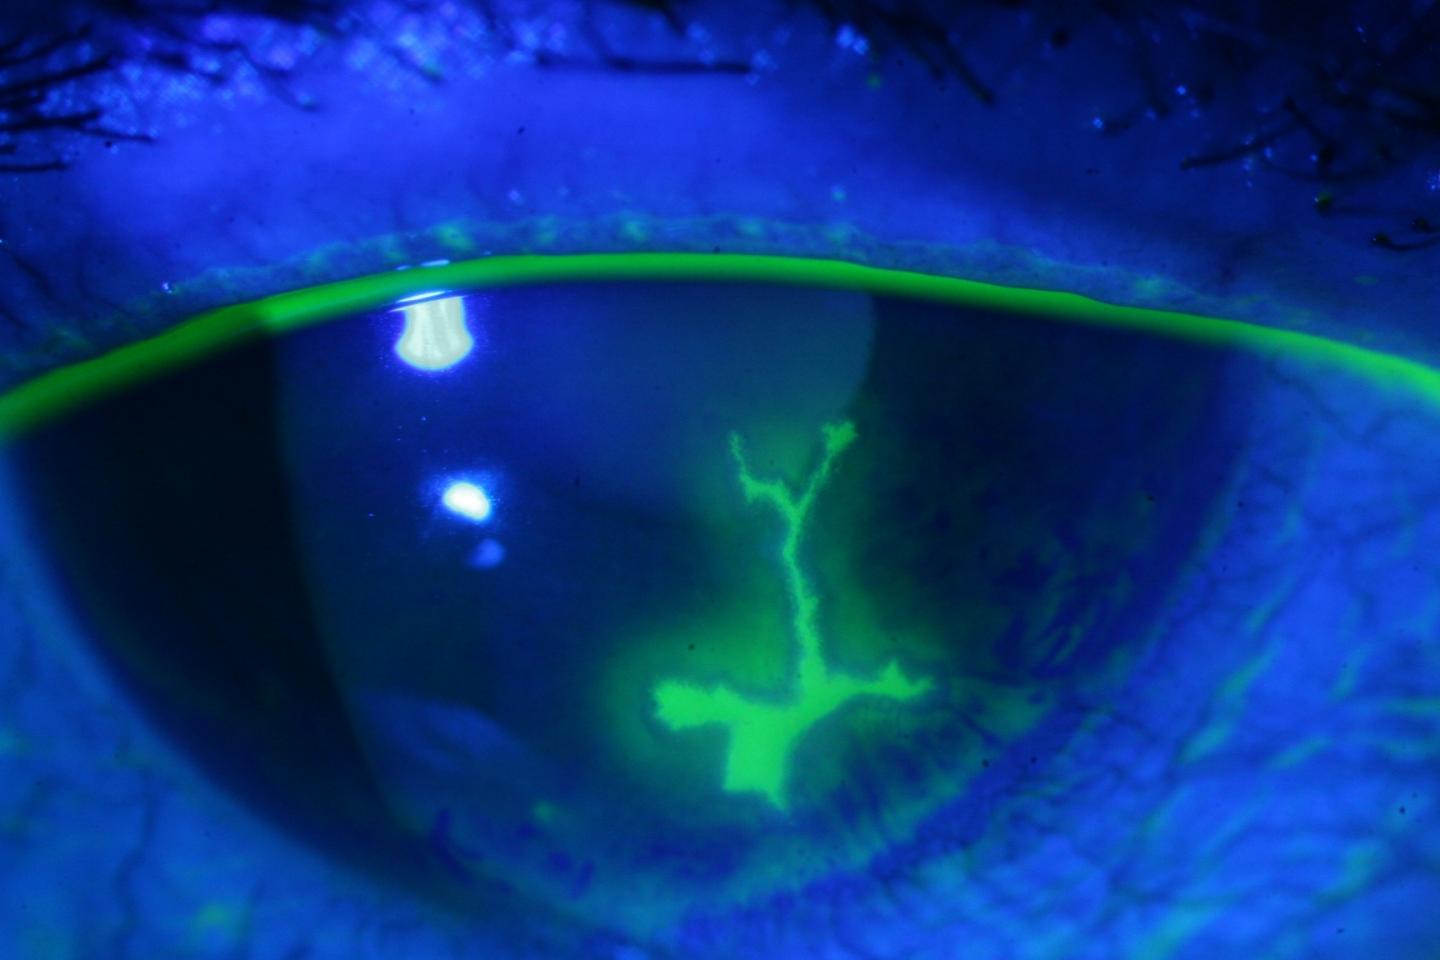

Caption: Human eye with herpes keratitis, a disease caused by reactivation of latent HSV-1 that can lead to impaired vision and blindness.

Image Credit: Hilda Schenk, University Medical Center Utrecht.